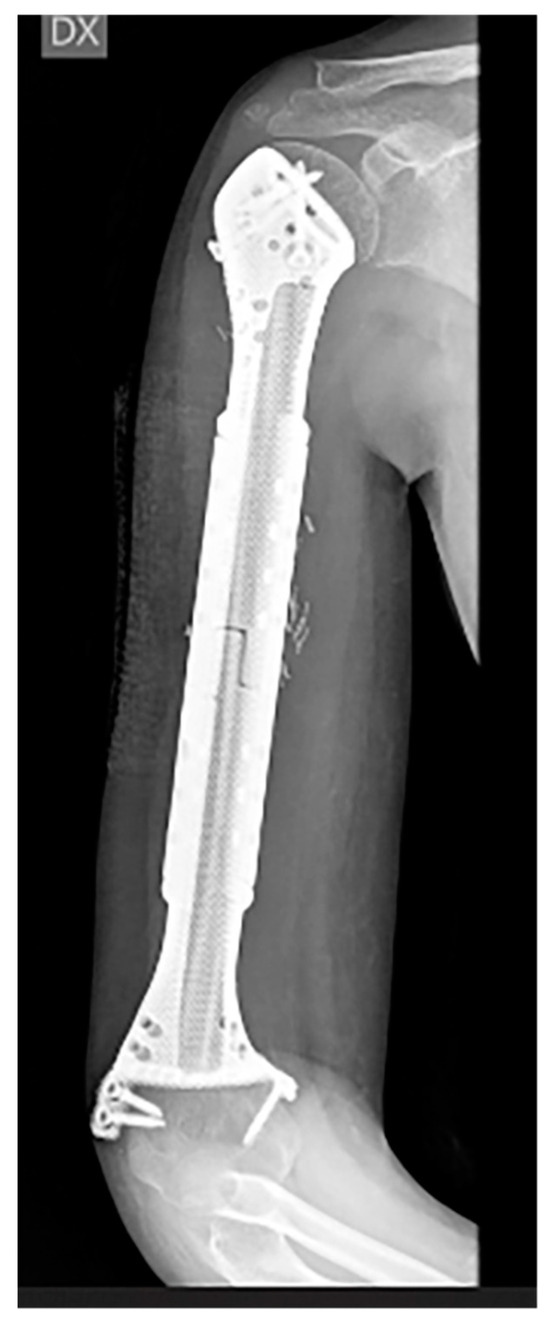

Biological Prosthesis (Hollow 3D-Printed Titanium Custom-Made Prosthesis and Bone Graft) for Humeral Reconstruction in Pediatric Oncologic Patients: Surgical Indications and Results

- Beltrami, G.; Ristori, G.; Nucci, A.M.; Galeotti, A.; Tamburini, A.; Scoccianti, G.; Campanacci, D.; Innocenti, M.; Capanna, R. Custom-made 3D-printed implants as novel approach to reconstructive surgery after oncologic resection in pediatric patients. J. Clin. Med. 2021, 10, 1056. [Google Scholar] [CrossRef] [PubMed]

- Beltrami, G.; Ristori, G.; Galeotti, A.; Scoccianti, G.; Tamburini, A.; Campanacci, D.; Capanna, R.; Innocenti, M. A hollow, custom-made prosthesis combined with a vascularized flap and bone graft for skeletal reconstruction after bone tumour resection. Surg. Oncol. 2021, 36, 56–60. [Google Scholar] [CrossRef]

- Beltrami, G.; Nucci, A.M.; Tamburini, A.; Innocenti, M. Custom-made 3D-printed prosthesis and free vascularised fibula for humeral reconstruction after osteosarcoma resection in a 13-year-old patient. BMJ Case Rep. 2021, 14, e240726. [Google Scholar] [CrossRef]